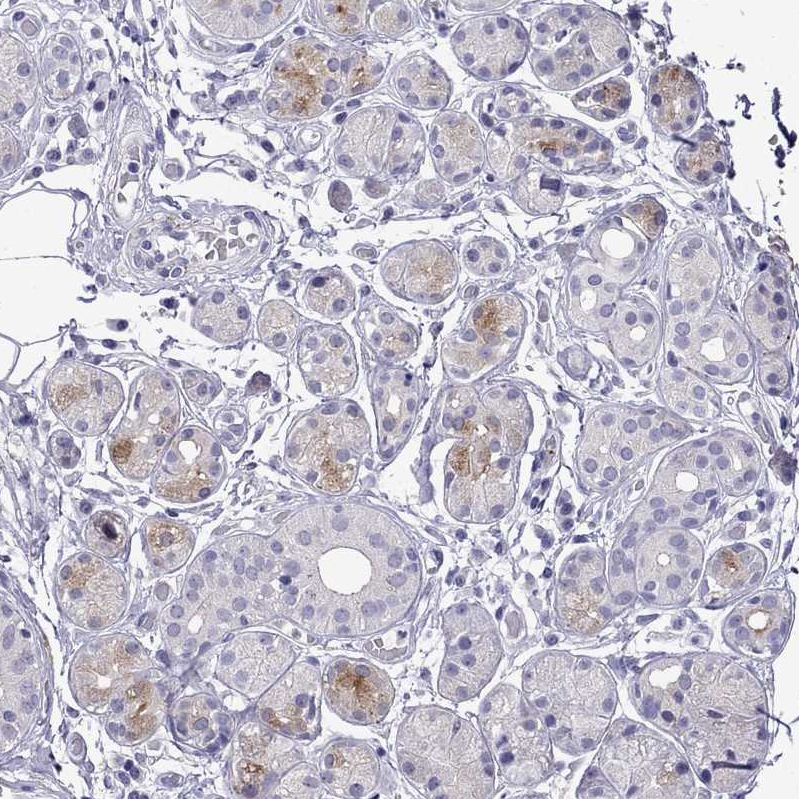

Immunohistochemical staining of human breast shows moderate cytoplasmic positivity in glandular cells.